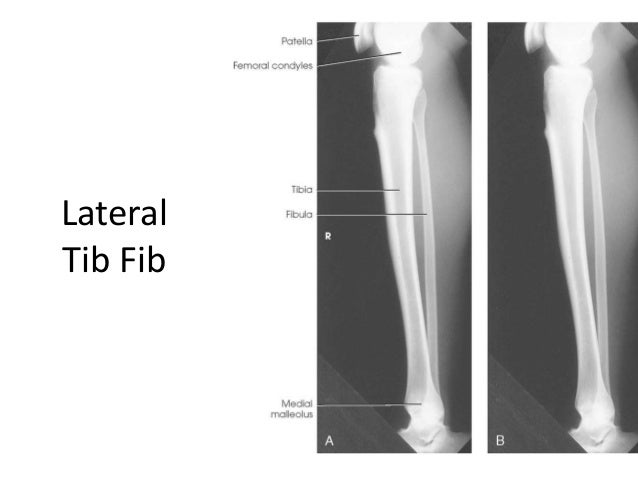

Tib fib anatomy. The university of minnesota is an equal opportunity educator and employer. The tibiafibula is comprised of an anteroposterior ap and lateral radiograph. Medial malleolus tibia tibial tuberosity lateral malleolus fibula fibular head.

Tib fib anatomy bones and features of the lower legs. The tibiafibula is comprised of an anteroposterior ap and lateral radiograph. On the lateral aspect of the distal tibia.

Tibia and fibula bone anatomy tibia and fibula memory trick. The series is often used in emergency departments to evaluate the entirety of the tibia and fibula after trauma.